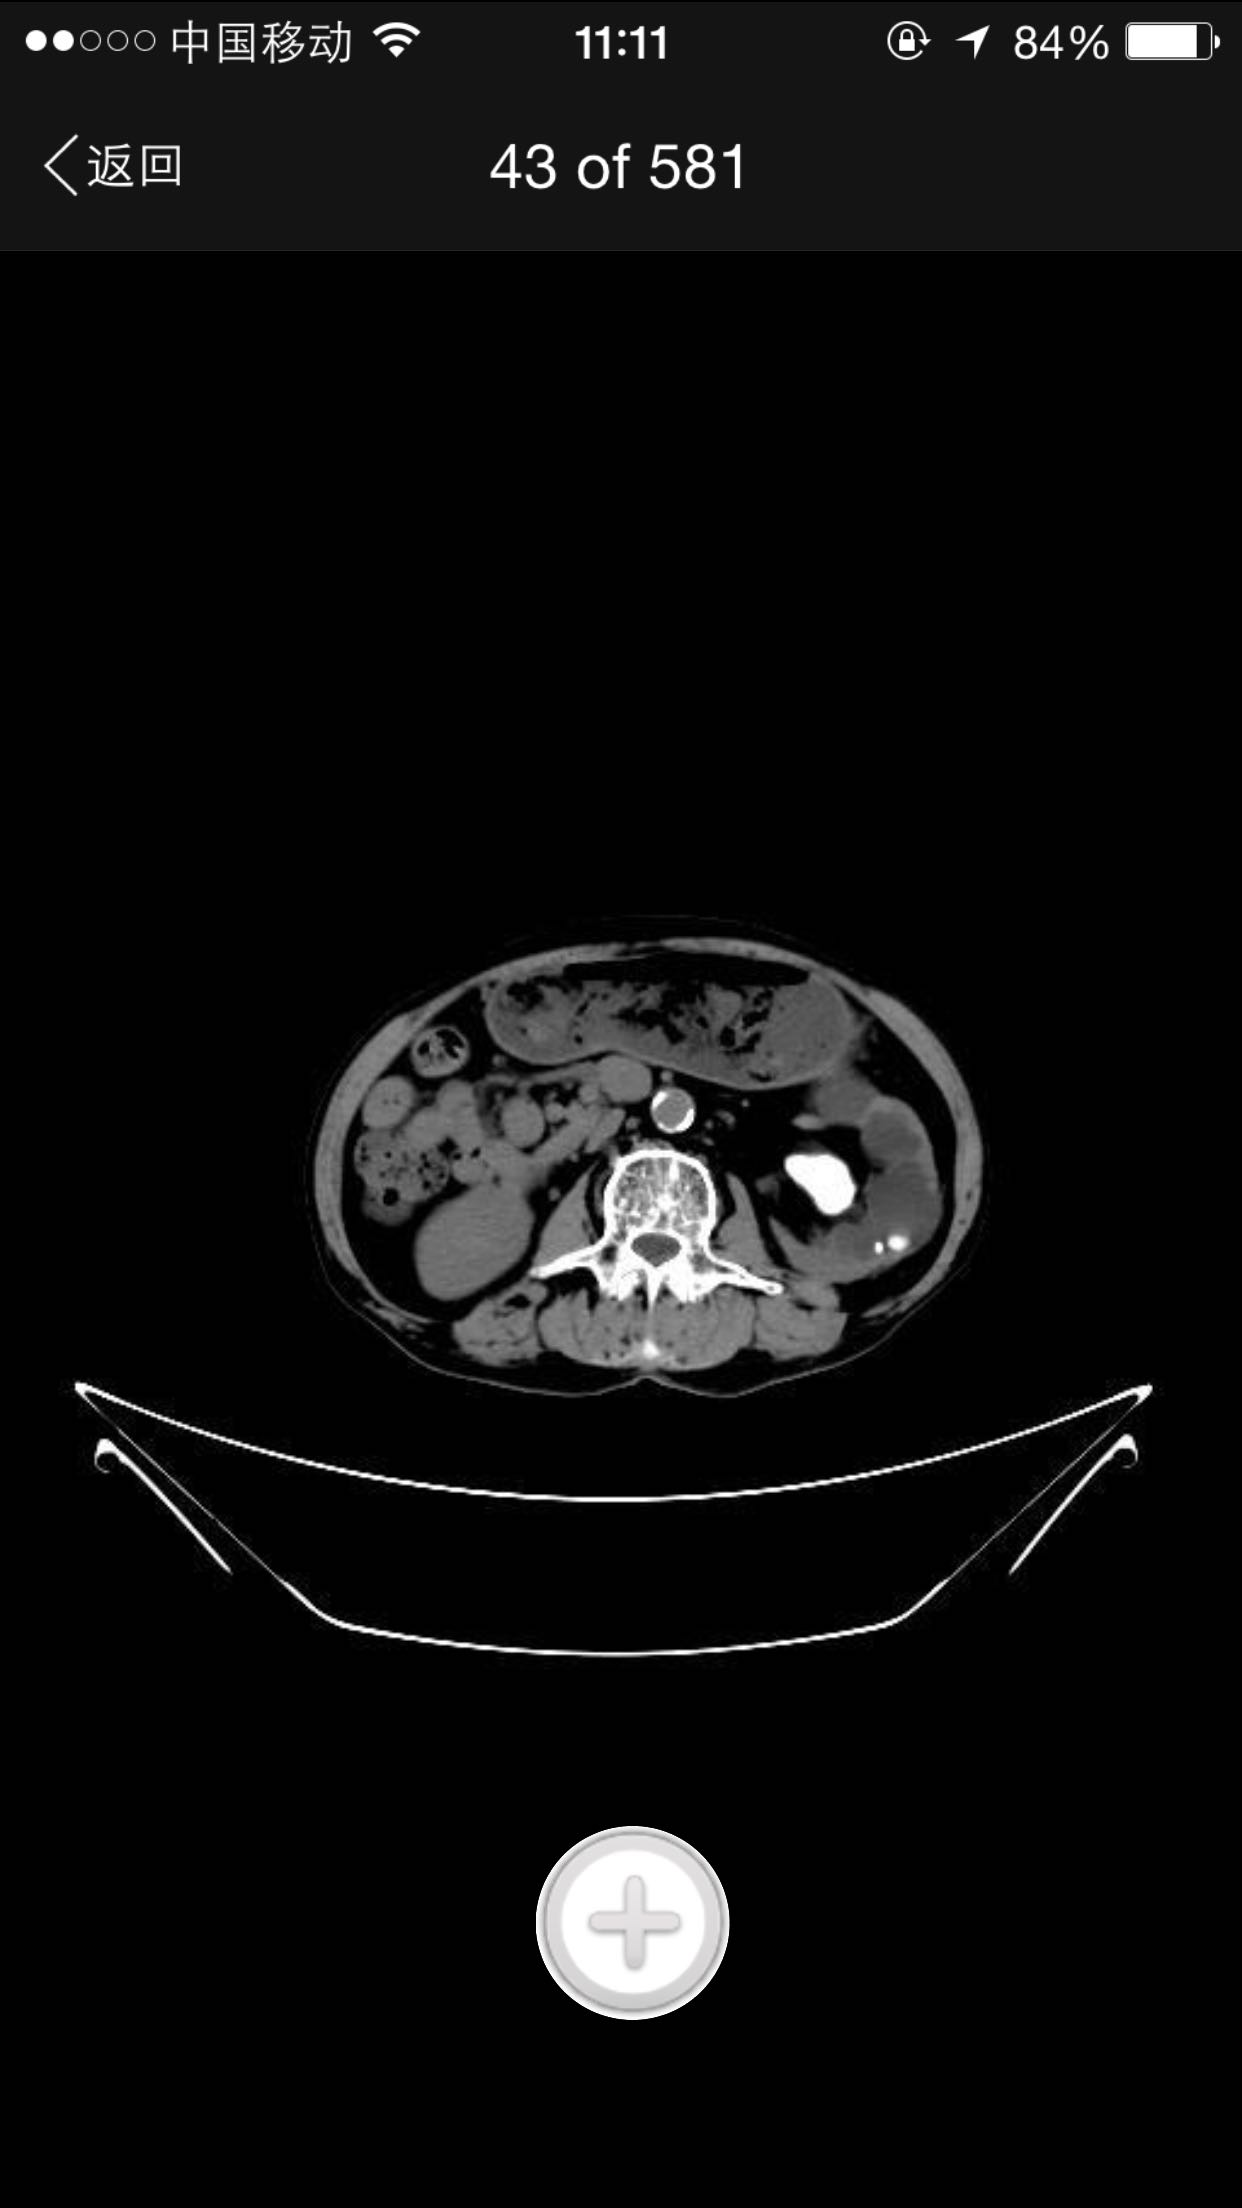

排尿困难,尿潴留入院。诊为前列腺增生症,拟行手术治疗。完善术前检查,泌尿系CT检查发现左肾占位,左肾结石并左肾重度积水,左肾萎缩等。既往患者肺结核病史,服药控制半年余。

查体:腹平软,无压痛及反跳痛,无肾区叩痛,肛诊前列腺明显增大,中央沟消失,无硬结,无压痛。术前强化CT提示左肾癌。

术前诊断:1、左肾癌2、左肾结石3、左肾积水4、左肾萎缩5、前列腺增生6、肺结核 入院后完善检查,拟行TURP,因发现左肾癌,改为先行肾手术。患者左肾癌,同时左肾结石,肾萎缩,决定行根治性肾切除,拟腹腔镜下手术,患者家属不同意,改开放手术,全麻下行根治性左肾切除。术后剖开标本如下图,肿瘤位于肾上极,中间黑色为结石。

术后病理肾乳头状肾细胞癌,侵及肾被膜。